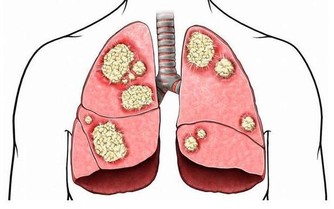

不僅如此,酒精(飲料)早已被世界衛生組織下屬的國際癌症研究機構(IARC)列為I類致癌物。

全世界5.5%的癌症發生和5.8%的癌症死亡是由酒精引起的,也就是說每18個癌症裡,就有1個是喝酒喝出來的。

飲酒引起的癌症類型也很多,比如乳腺癌、結直腸癌、肝癌、食管癌、胃癌和胰腺癌等都有直接關係。當然,和酒關係最密切的癌症類型,還有口腔癌,喉癌,食管癌等。